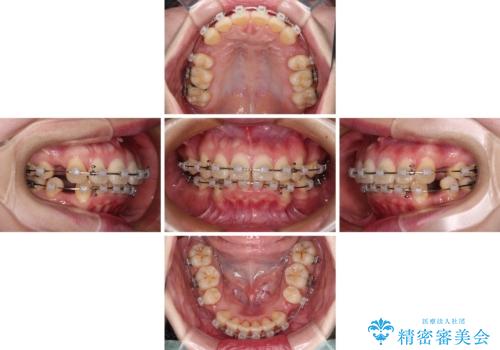

- クリアブラケット

- 1年10ヶ月

- 下唇に跡がつくほどに飛び出した上顎前歯を気にして来院された患者様です。

来院された時から4本の抜歯が必要であることを理解されていらしており、通法通り上下左右の第一小臼歯4本を抜歯し、ワイヤー装置にて矯正治療を行うこととしました。